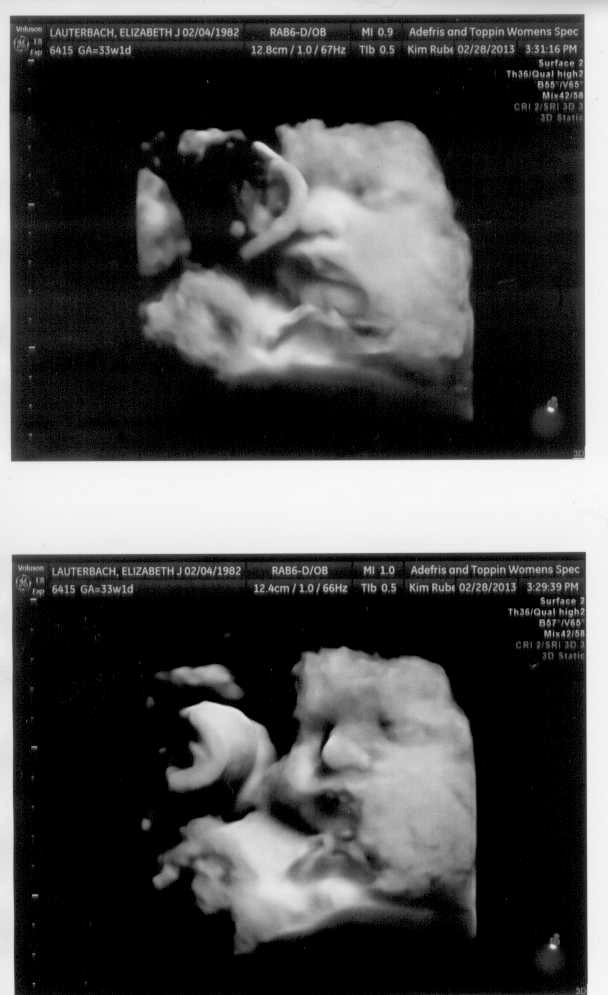

Sometimes our collections of experiences give us a glimpse into the lives of others. On Friday, I saw some complete strangers, but I instantly knew what happened.

Sometimes our collections of experiences give us a glimpse into the lives of others. On Friday, I saw some complete strangers, but I instantly knew what happened.